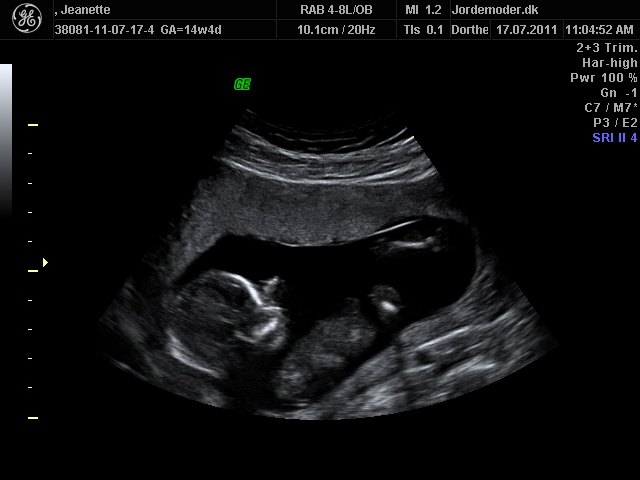

Så kom dagen for kønsscanningen.....

Svaret blev.... dam dam dam dam... ET BARN.. griner...

Ej hende der skulle scanne var ikke sikker på barnets køn, så vi skal op til kønsscanning igen om nogle dage.... men men men dejligt nok, for så får vi vores lille skat at se igen på skærmen....

Vedhæftede fotos (klik for at se i fuld størrelse)